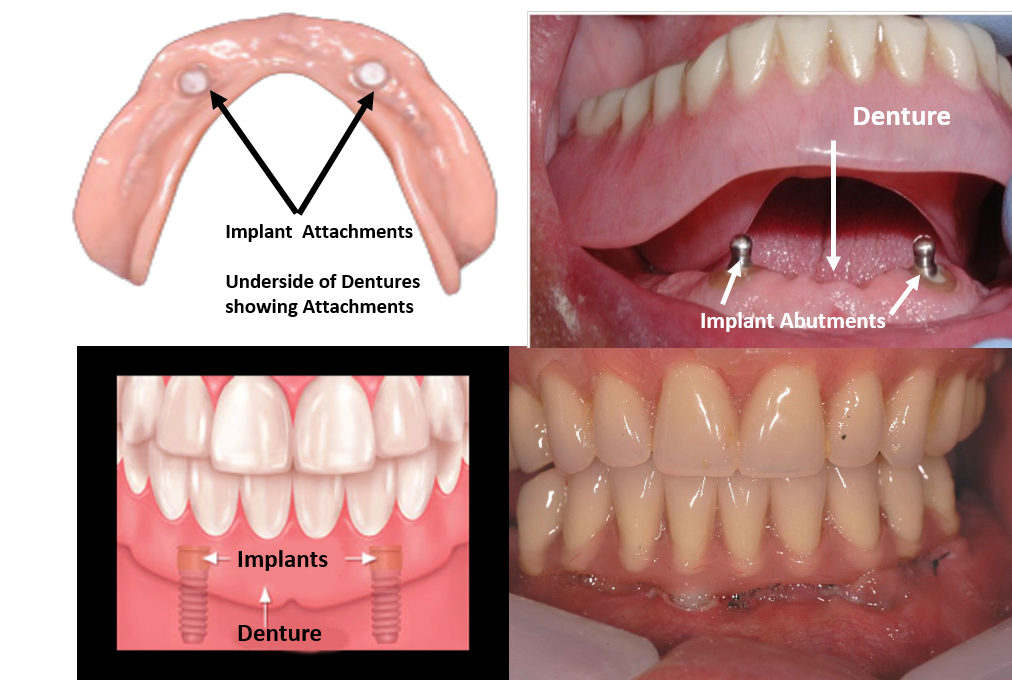

Implant-Retained Overdentures Implant Attachments, underside of dentures showing over denture Attachments:  Ball attachments, help to snap a denture into place – Enhanced Stability

Implant-supported Denture is securely anchored to the jawbone with dental implants, offering enhanced stability compared to traditional dentures that rest on the gums.

Enhanced Stability: Only 2 to 4 implants are typically needed to stabilize a full denture (12-14 teeth), providing a secure fit with significant cost reduction compared to full-mouth fixed _Implants.

Improved Comfort: Eliminates issues like slippage, especially in the lower jaw.

Snap-On Design: Easily removable and reattached for patient convenience, while providing excellent stability and balance, by virtue of the support given by Implants.

Better Balance: Provides superior stability over traditional dentures.